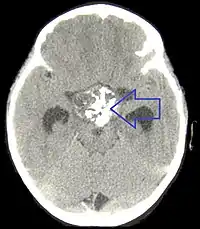

颅咽管瘤

颅咽管瘤是发生于颅咽管(Landzert's canal)的先天性良性肿瘤,多见于少年和儿童,从胚胎期颅咽管的残余组织发生,好发于蝶鞍上垂体结节部上端,少数位于鞍内,向鞍上发展,个别见于蝶窦或咽后壁等处。生長緩慢各人病情差異大,有十多歲發病也有四十歲以上才發病。